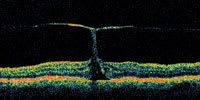

Figure 1. OCT showing early macular hole formation. The lateral separation is less than 50 μm. |

A central clinical challenge has been accurately diagnosing early macular holes which may be mimicked by many other conditions.34,35 No imaging modality has enhanced our diagnostic capability more than the OCT; superior imaging capabilities have improved diagnostic accuracy, clinical monitoring, and postoperative assessment.36-38 The OCT unequivocally demonstrates early stages of full-thickness macular holes (Figure 1), and allows distinction of pseudohole and pre-macular hole conditions in almost all instances. Fluid accumulation in early, presumed pre-macular hole stages have been corroborated by OCT observations (Figure 2). Serial images have been reported showing the progression from apparent impending macular holes to full thickness macular holes.39-42 It has depicted many other configurations that might be in the spectrum of lamellar or pre-macular hole conditions (Figure 3 and 4).